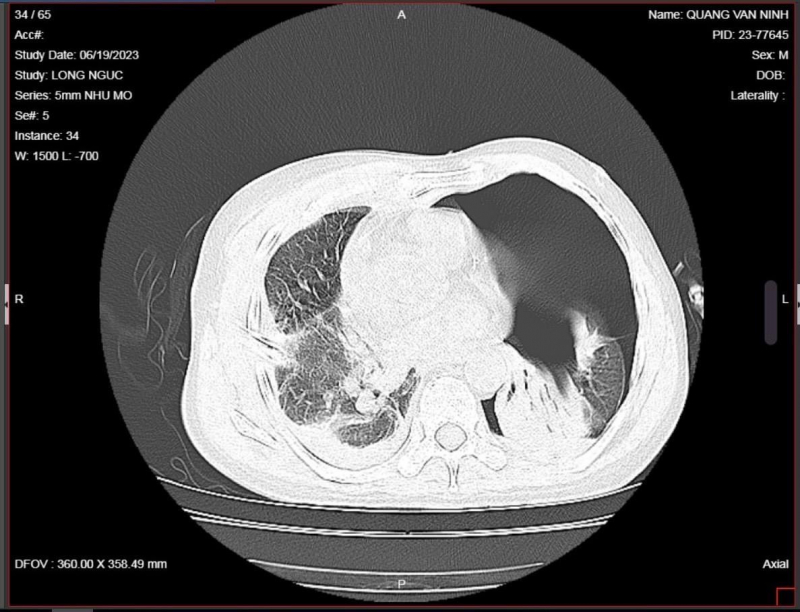

Qua thăm khám và thực hiện các chỉ định cận lâm sàng, kết quả hội chẩn liên khoa chẩn đoán bệnh nhân bị đa chấn thương, vết thương phức tạp cổ chân phải, chấn thương lồng ngực, gãy nhiều xương sườn hai bên, vết thương thấu ngực dẫn đến tràn dịch màng phổi bên phải, tràn khí màng phổi trái, gây xẹp phổi, suy hô hấp.

Ngay khi vào khoa Cấp cứu, bệnh nhân đã được đặt thở máy và chuyển thẳng lên phòng mổ. Tại đây, các bác sĩ Trung tâm chấn thương chỉnh hình tiến hành phẫu thuật dẫn lưu khoang màng phổi 2 bên, hút liên tục áp lực âm, xử lý vết thương phức tạp vùng cổ chân phải.

Quá trình điều trị hậu phẫu tại phòng hồi sức sau mổ, bệnh nhân được hồi sức tích cực: Thở máy, truyền dịch, truyền máu và giảm đau liên tục bằng kỹ thuật gây tê ngoài màng cứng vùng ngực. Qua gần 20 ngày điều trị bệnh nhân đã ổn định.